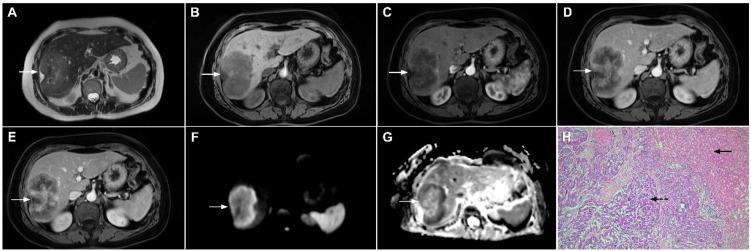

Intrahepatic cholangiocarcinoma (ICC) is the second most common primary hepatic malignancy, with mass-forming growth pattern being the most common. The typical imaging appearance of mass-forming ICC (mICC) consists of irregular ring enhancement in the arterial phase followed by the progressive central enhancement on portal venous and delayed phases. However, atypical imaging presentation in the form of hypervascular mICC might also be seen, which can be attributed to distinct pathological characteristics. Ancillary imaging features such as lobular shape, capsular retraction, segmental biliary dilatation, and vascular encasement favor the diagnosis of mICC. Nevertheless, these radiological findings may also be present in certain benign conditions such as focal confluent fibrosis, sclerosing hemangioma, organizing hepatic abscess, or the pseudosolid form of hydatid disease. In addition, a few malignant lesions including primary liver lymphoma, hemangioendothelioma, solitary hypovascular liver metastases, and atypical forms of hepatocellular carcinoma (HCC), such as scirrhous HCC, infiltrative HCC, and poorly differentiated HCC, may also pose a diagnostic dilemma by simulating mICC in imaging studies. Diffusion-weighted imaging and the use of hepatobiliary contrast agents might be helpful for differential diagnosis in certain cases. The aim of this manuscript is to provide a comprehensive overview of mICC imaging features and to describe useful tips for differential diagnosis with its potential mimickers.

肝内胆管细胞癌(ICC)是第二常见的原发性肝恶性肿瘤,以肿块型生长方式最为常见。肿块型肝内胆管细胞癌(mICC)的典型影像学表现为动脉期不规则环状强化,随后门静脉期和延迟期进行性中央强化。然而,也可能出现富血供型 mICC 的不典型表现,这可归因于其独特的病理特征。辅助影像学特征,如小叶形状、包膜回缩、节段性胆管扩张和血管包绕,有助于 mICC 的诊断。然而,这些影像学表现也可能存在于某些良性病变中,如局灶性融合性纤维增生、硬化性血管瘤、化脓性肝脓肿或包虫病的假实质性形式。此外,少数恶性病变,包括原发性肝淋巴瘤、血管内皮细胞瘤、孤立性低血供肝转移瘤和不典型的肝细胞癌(HCC)形式,如硬癌型 HCC、浸润性 HCC 和低分化 HCC,也可能在影像学研究中模拟 mICC,导致诊断困难。弥散加权成像和肝胆对比剂的使用可能有助于某些情况下的鉴别诊断。本文旨在全面概述 mICC 的影像学特征,并描述与潜在类似物进行鉴别诊断的有用技巧。